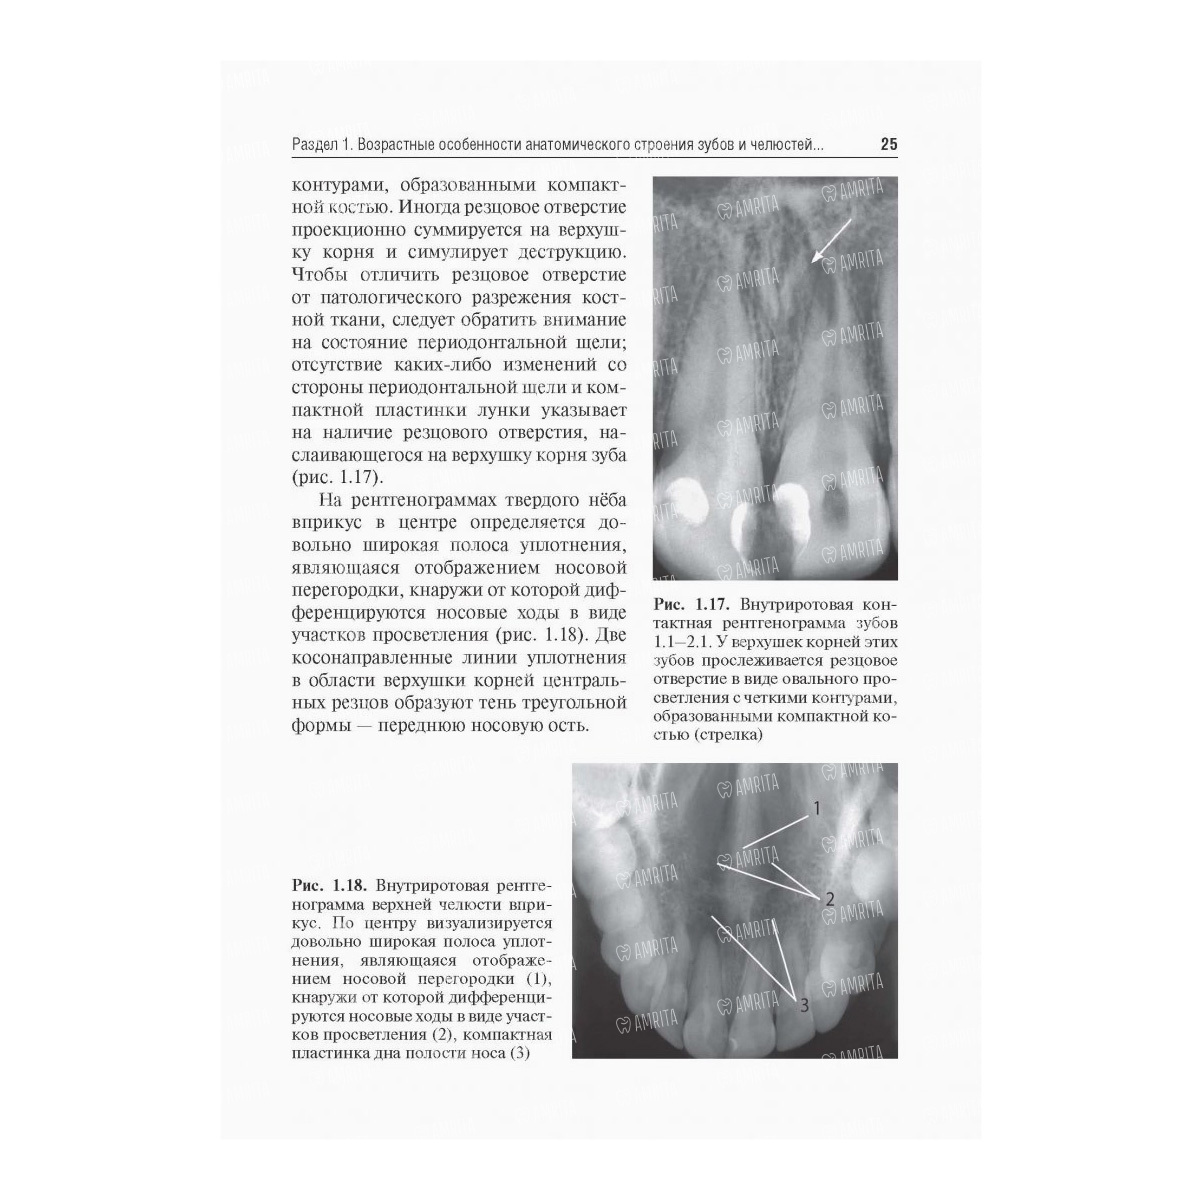

В учебном пособии представлены как современные, так и традиционные методики и проекции рентгенологического исследования зубочелюстной системы в норме и при патологии. Освещены вопросы развития зубов и челюстей, рентгеноанатомии, рентгеносемиотики при заболеваниях челюстно-лицевой области, а также положения о радиационных нагрузках и методы защиты. Краткие описания рентгенограмм позволяют детально ознакомиться с рентгенологической картиной широкого круга различных заболеваний. Впервые представлен важный аспект - объем рентгенологического исследования первичного стоматологического пациента. Проиллюстрированы особенности рентгенологического контроля в оценке качества эндодонтического и хирургического лечения.